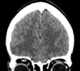

A carotid-cavernous fistula results from an abnormal communication between the arterial and venous systems within the cavernous sinus in the skull. It is a type of arteriovenous fistula. [Source: Wikipedia ]